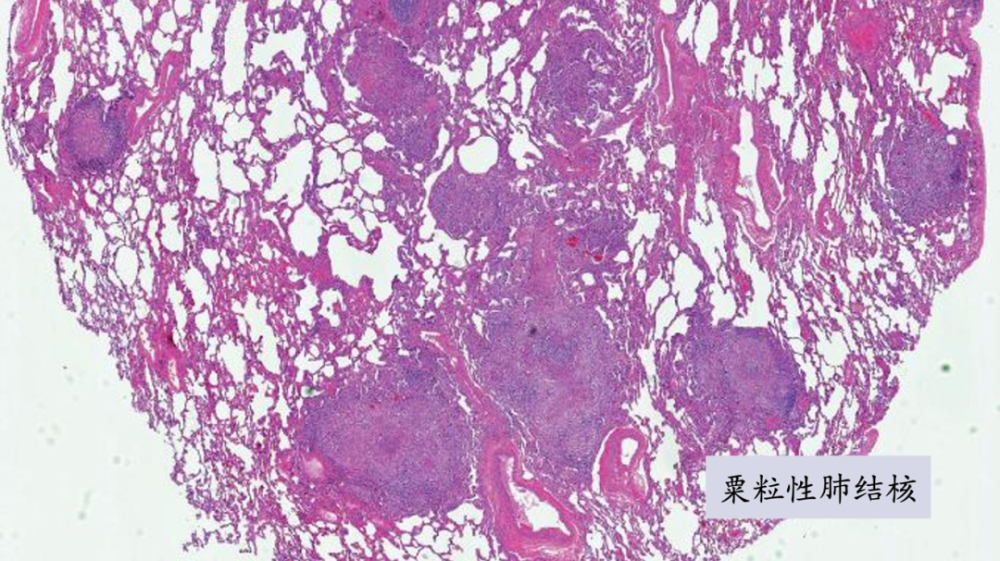

下图是一个粟粒性肺结核的病理切片.

40×猪肺结核